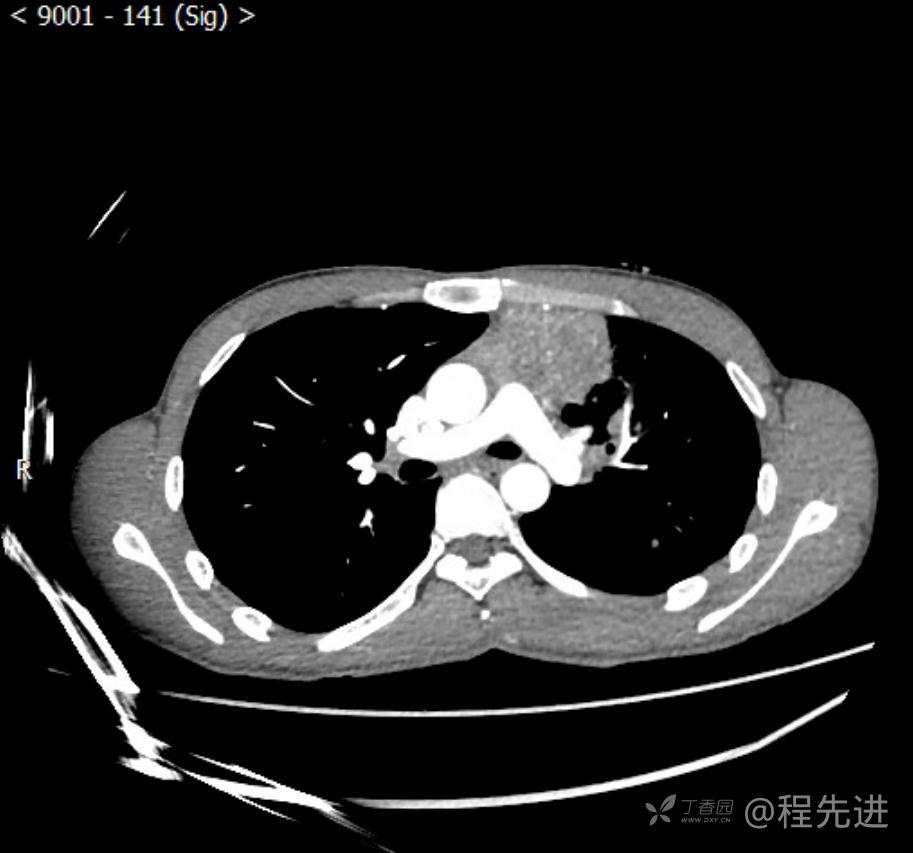

主诉:反复咳嗽1月,发现“纵隔”占位半月,乏力10余天。

现病史:患者1月前无明显诱因出现咳嗽,以夜间为著,伴有少量白痰,无发热,无胸痛、咯血,无痰中带血,未予重视,半月前外院行胸部CT检查发现“左前上纵隔”占位,未予进一步检查及治疗。近10余天自觉乏力,逐渐加重。